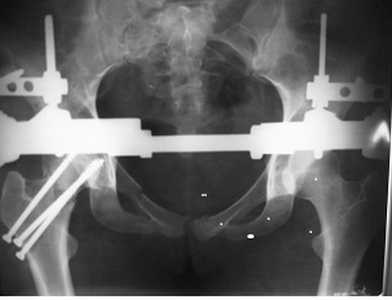

Re: перелом костей таза

У нас был такой случай, прооперировал на 3 сутки. Результат полное выздоровление.